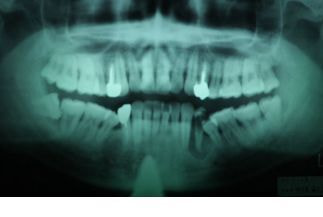

根管治療後の痛みの原因は、実は治療している歯でない場合や不適切な根管治療によって起こる場合、急性の歯髄炎によるものや急性根尖性歯周炎によるものなど様々です。

抜歯を勧められた場合でも、実は根管治療時の感染のコントロールが不十分なことが原因で治っていないケースが結構あり、そのような場合は根管治療で残すことが出来ます。